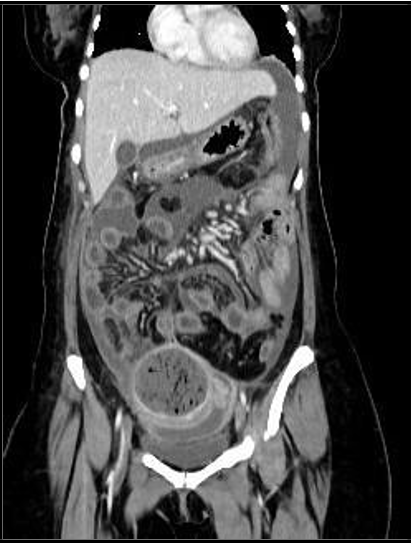

A CT scan of the abdomen and pelvis with contrast was performed to determine the cause of sepsis. It revealed a large, thick, enhancing walled-off area in the pelvis adjacent to the fundus of the uterus, containing multiple internal air locules with indistinct walls at places, and continuing air tracks. (Figure 1, 2). This represented an infected embolectomy-treated  subserosal  fibroid.  There  were  multiple intercommunicating pelvic infection collections in the cul-de-sac and vesico-uterine pouch (Figure 3). Diffuse peritonitis, omentomesenteric congestion, and edematous bowel loops were observed. Multiple prominent pelvic sidewall nodes were also noted. Therefore, rupture of pyomyoma with intraperitoneal spillage of infected content resulting in peritonitis is suggested.

Figure 2: Coronal images of contrast enhanced CT scan showing diffuse peritoneal reaction and fluid.